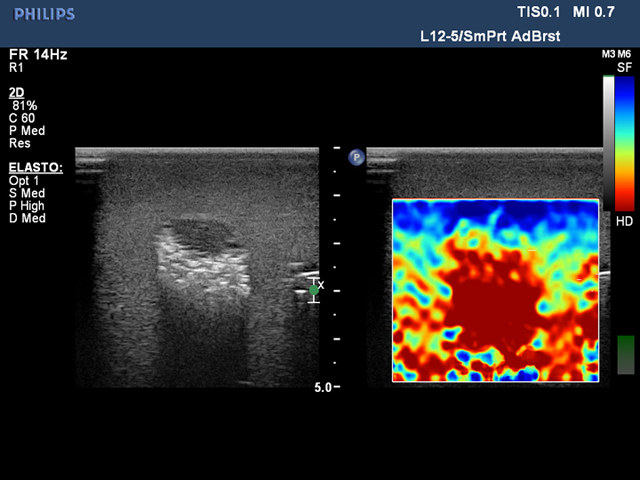

乳房超声弹性成像训练模型给用户提供了一个很好的培训平台,用户可以通过使用本产品练习乳腺弹性成像所需的技能。模型内部的肿块大小不同,便于学生先练习较大病灶的识别和扫描,待熟练后再练习扫描尺寸更小的病灶。